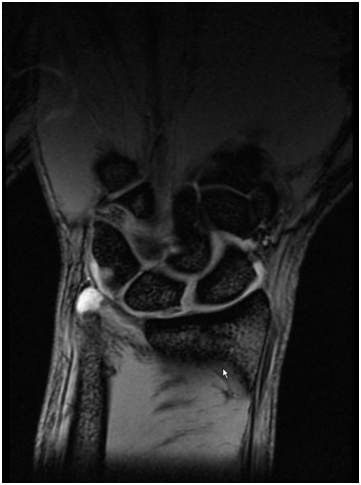

These injuries are relatively common and are either frequently missed or underestimated. The scapholunate ligament (SLL) is a ligament in the central aspect of the wrist and is an important stabiliser of the wrist . It is therefore the equivalent of the “Cruciate” ligament of ACL of the knee. If it is seriously injured the patient can develop pain on load bearing esp doing press ups or lifting objects. Certain everyday tasks can become painful if seriously injured. If the injury is neglected, premature arthritis and collapse of the wrist may occur in certain situations.

After scaphoid fractures, the SLL is probably the most commonly missed injury and this can have potentially detrimental effects for the patient.

An early MRI scan is required to make a prompt diagnosis. If diagnosed early (within 6 weeks) a repair of the ligament is possible. When diagnosed later, reconstruction using tendon graft is often required. The latter is more complex surgery and therefore an early diagnosis is recommended.